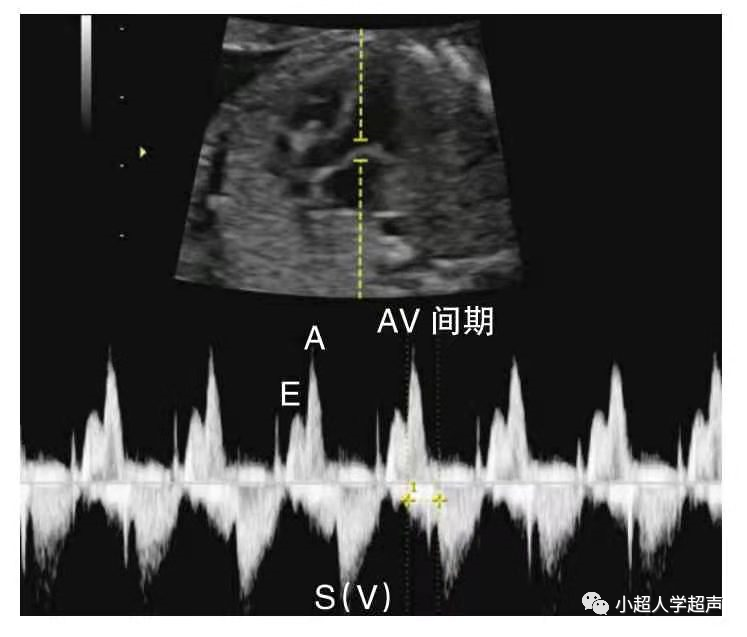

3)三度房室传导阻滞

完全性房室传导阻滞(CAVB)是指胎儿心室率<80/min,心房律>心室律,心房壁和心室壁运动曲线节律分离、互不相关,即心房、心室各跳各的,为完全性房室传导阻滞。